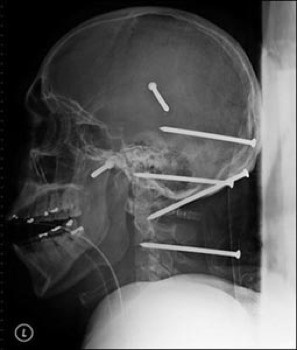

![]() |

| 6 chiếc đinh nằm trong hộp sọ của một người |